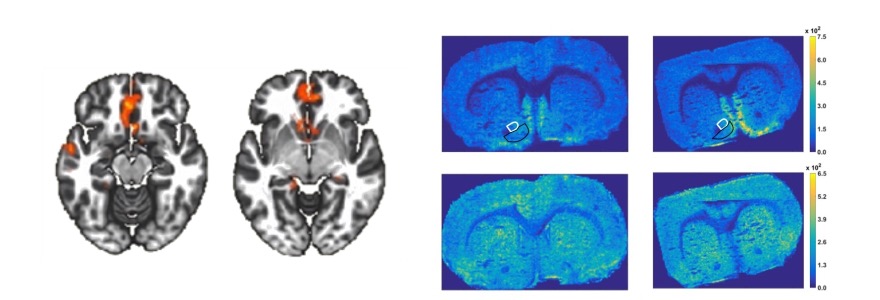

In animal models, the researchers are using an innovative open-source vaping system developed by Schulich Medicine & Dentistry researchers to simulate human consumption patterns of nicotine through vapes. This method allows the team to examine how nicotine affects brain areas linked to mood and anxiety disorders.

“We are imaging and quantifying neurotransmitters like GABA, glutamate, and dopamine in the brain post-nicotine exposure. These neurotransmitters are known to be dysregulated in mood and anxiety disorders, providing a crucial link between nicotine exposure and mental health risks.”